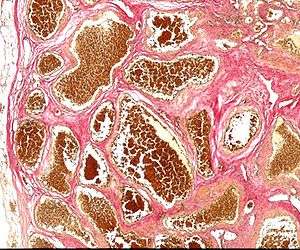

Histology of a cavernous hemangioma | |

Central nervous system cavernous hemangioma is a cavernous hemangioma that arises in the central nervous system (CNS). It can be considered to be a variant of hemangioma, and is characterized by grossly large dilated blood vessels and large vascular channels, less well circumscribed, and more involved with deep structures, with a single layer of endothelium and an absence of neuronal tissue within the lesions. These thinly walled vessels resemble sinusoidal cavities filled with stagnant blood. Blood vessels in patients with cerebral cavernous malformations (CCM) can range from a few millimeters to several centimeters in diameter. Most lesions occur in the brain, but any organ may be involved.[1]